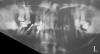

Гаша Опубликовано 29 июня, 2009 Поделиться Опубликовано 29 июня, 2009 Здравствуйте! Помогите, пожалуйста, советом. Пародонтоз - причем наследственный. Бабушка с сорока лет лишилась всех зубов, носила пластмассовые протезы, папа заменил собственные вынимающиеся пальцами зубы на протезы лет в пятьдесят. Я уже на грани. Многие зубы шатаются, несмотря на полоскания, рекомендованный стоматологами массаж десен, специальные пасты и все прочее. Вот снимок, что посоветуете: все выдирать? Или продолжать лечение? Если плохой снимок, могу еще попробовать переснять или помудрить с качеством. Заранее благодарна откликнувшимся практикующим врачам. Ссылка на комментарий

Dr. Surkin Опубликовано 29 июня, 2009 Поделиться Опубликовано 29 июня, 2009 (изменено) Здравствуйте! Помогите, пожалуйста, советом. Пародонтоз - причем наследственный. Бабушка с сорока лет лишилась всех зубов, носила пластмассовые протезы, папа заменил собственные вынимающиеся пальцами зубы на протезы лет в пятьдесят. Я уже на грани. Многие зубы шатаются, несмотря на полоскания, рекомендованный стоматологами массаж десен, специальные пасты и все прочее. Вот снимок, что посоветуете: все выдирать? Или продолжать лечение? Если плохой снимок, могу еще попробовать переснять или помудрить с качеством. Заранее благодарна откликнувшимся практикующим врачам. Думаю, что наследственность вторична.Много разрушенных зубов. Скорее всего много камней. Снимок не очень хороший, но на первое время сойдет. Надо найти нормального врача, начать с гигиены полости рта - снять камни, потом удалить совсем плохие зубы - например нижний 6-й справа, пролечить все кариесы, затем сделать новый снимок, оценить ситуацию заново и думать о вариантах протезирования. Изменено 29 июня, 2009 пользователем Dr. Surkin Ссылка на комментарий

Bier Опубликовано 30 июня, 2009 Поделиться Опубликовано 30 июня, 2009 в зависимости от выбора будущей конструкции наверху надо будет удалить либо все либо почти все зубы. Внизу мне плохо видно уровень костной ткани на этом снимке, но 46 и 38 надо удалять. Ссылка на комментарий